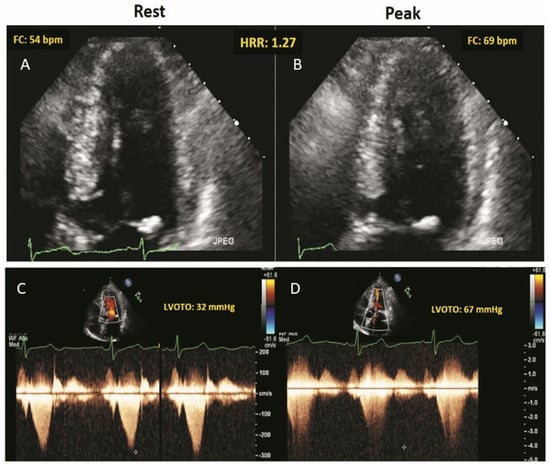

2.2. Resting and Stress Echocardiography

2.3. Heart Rate Reserve